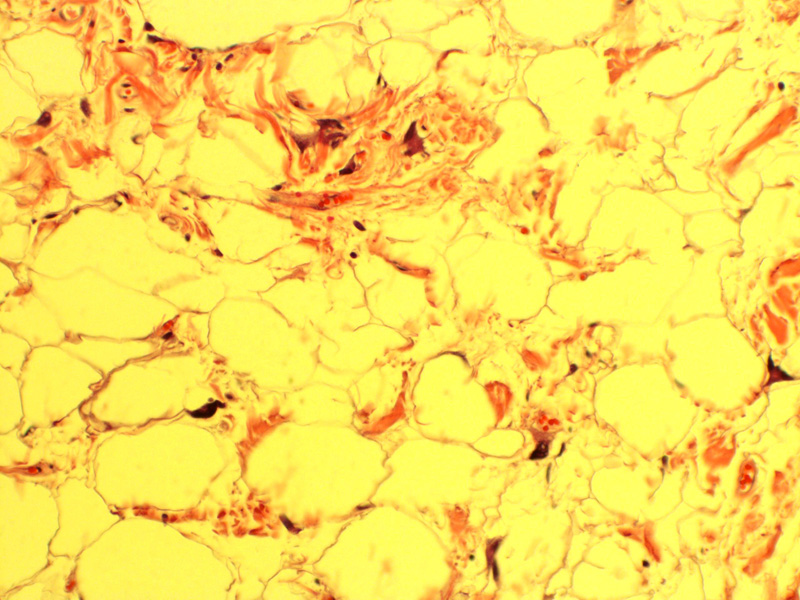

from librepathology.org

Spindle cell lipoma Libre Pathology

Spindle cell lipoma Libre Pathology Spindle Cell Lipoma Radiology To review the evaluation, diagnosis, and treatment of spindle cell lipoma (scl) with emphasis on the location of these. spindle cell lipoma (scl) is a benign adipocytic tumor that primarily occurs in the subcutis of the posterior. Spindle cell lipoma contains a varying mixture of mature adipocytes, bland spindle cells and ropy collagen fibers (cancer. to review the. Spindle Cell Lipoma Radiology.